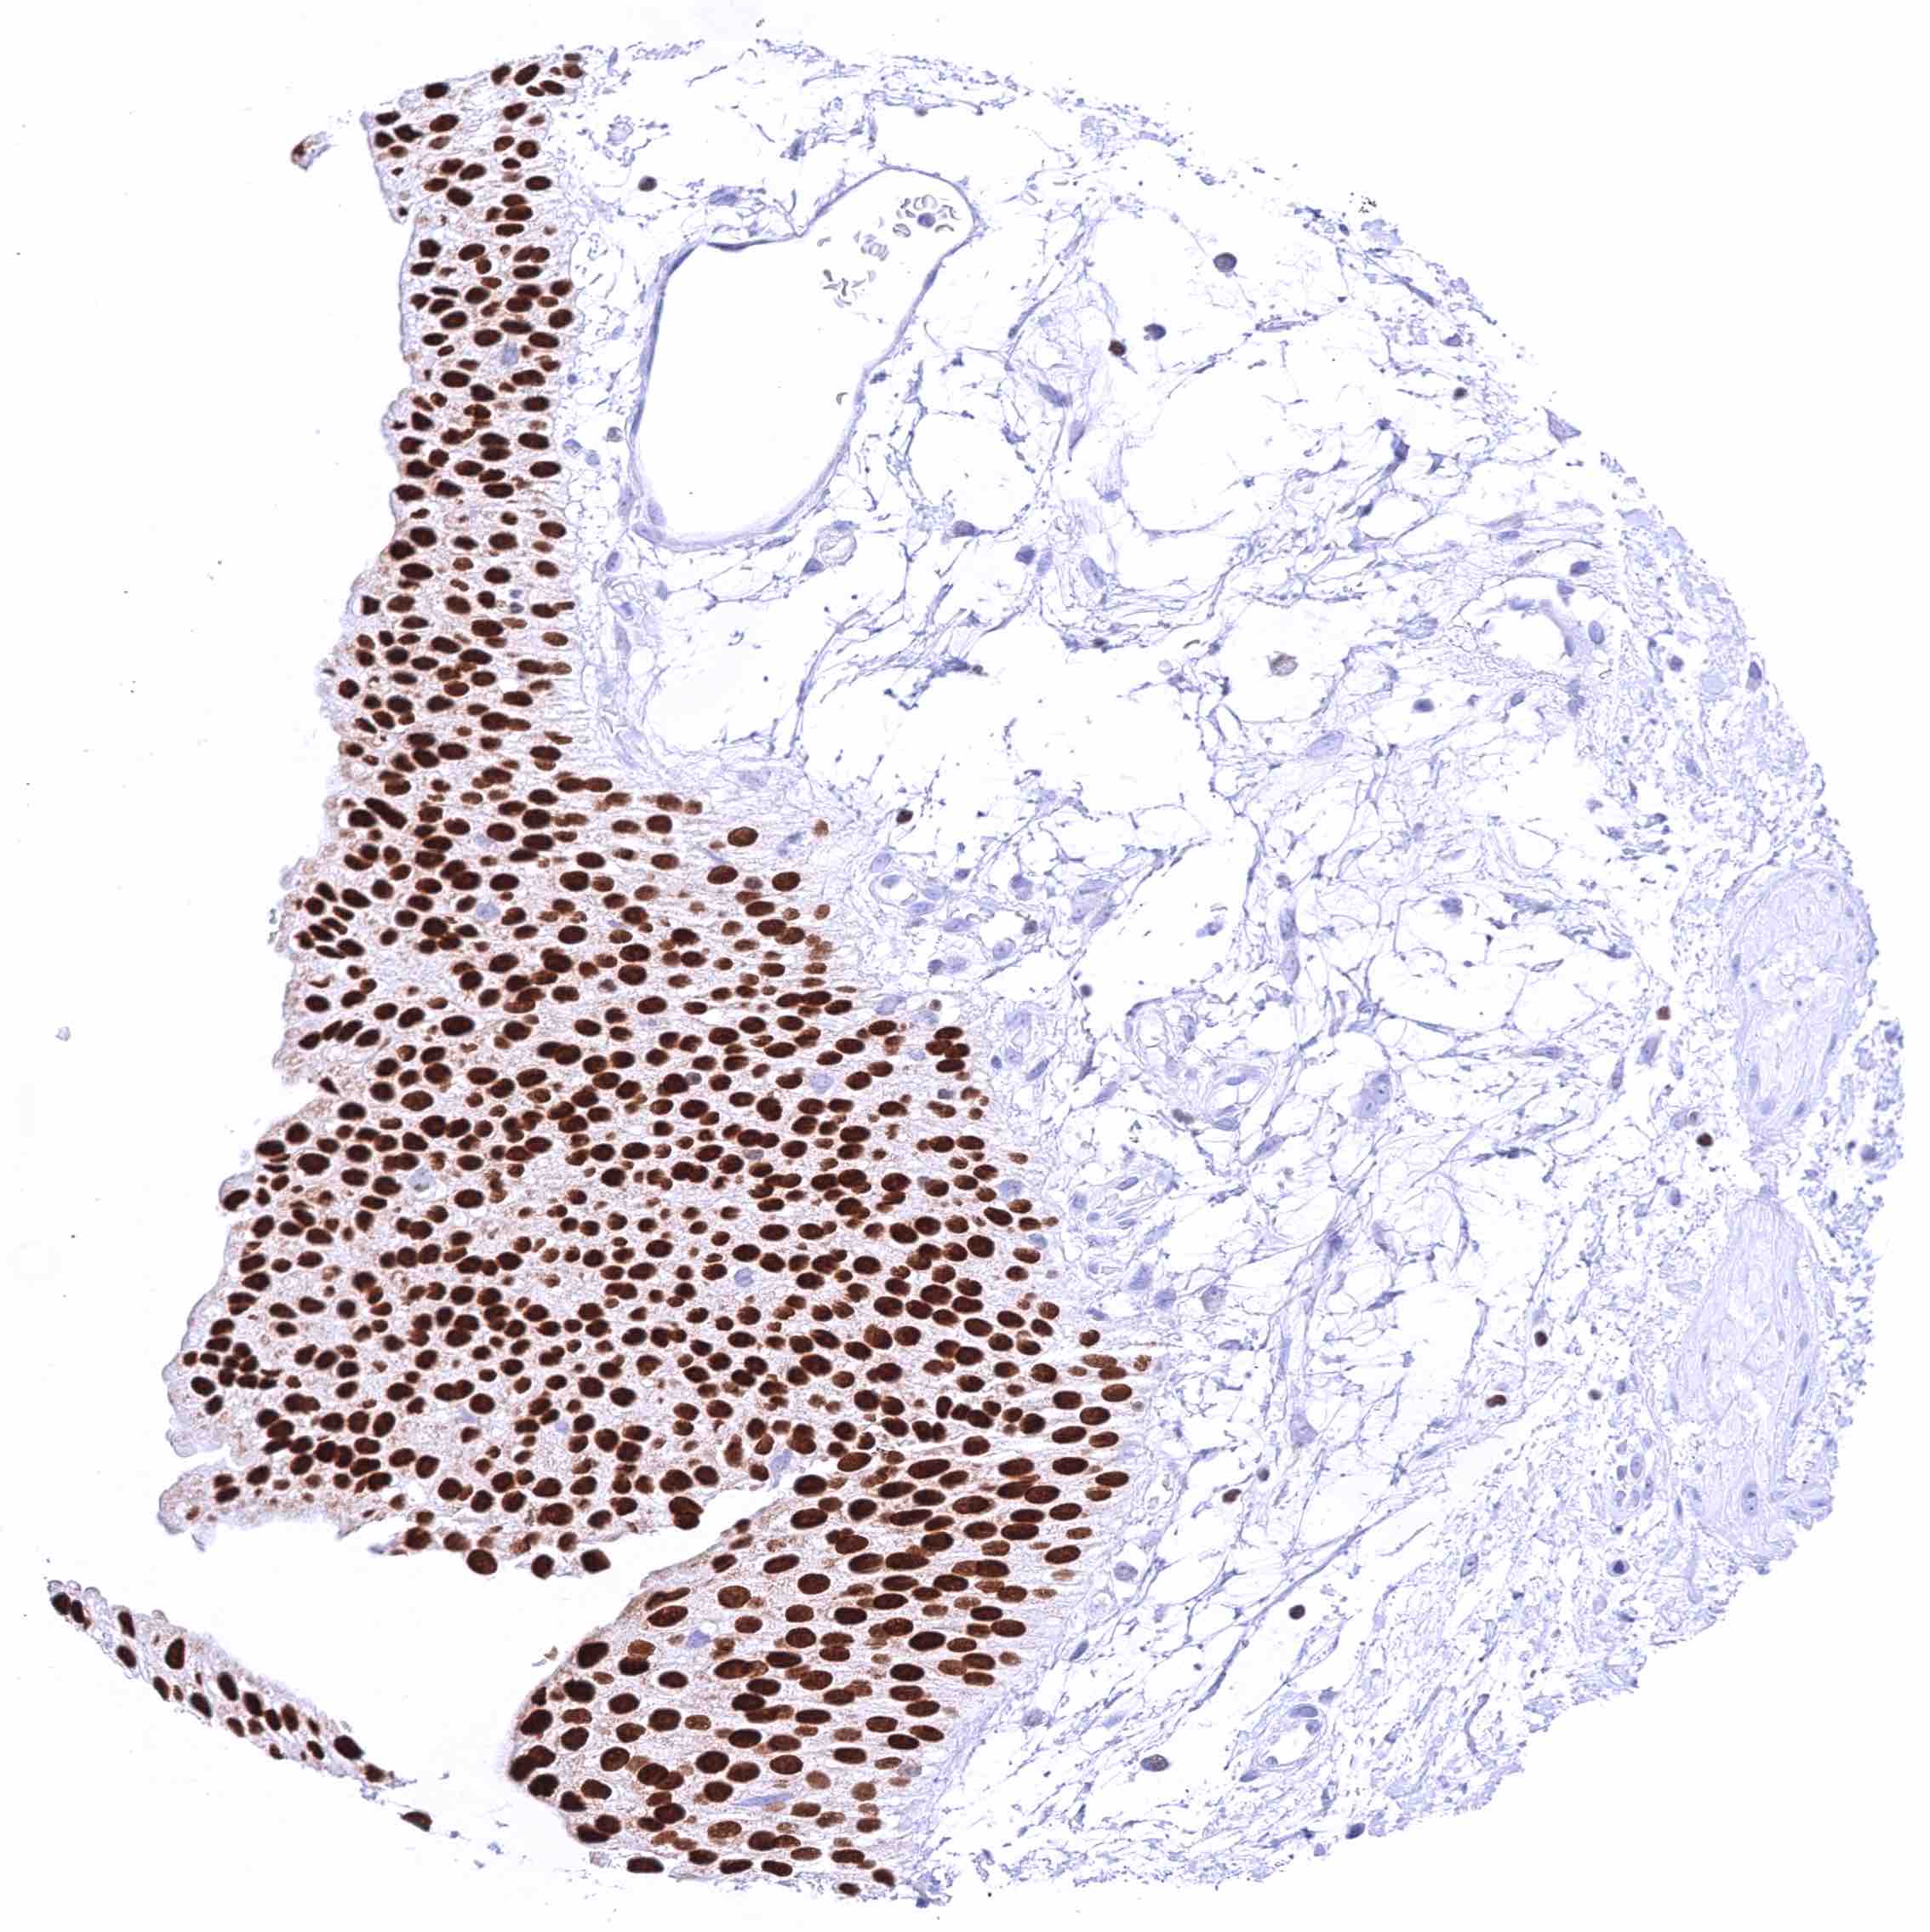

Kidney, pelvis, urothelium – Strong nuclear GATA3 positivity of all urothelial cells.